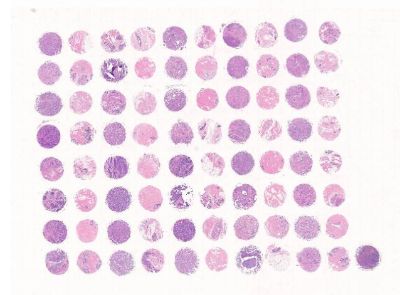

芯片加工

中科光华 芯片加工

专业芯片设计师为您量身打造高质量芯片。1. 芯片内设对照;2. 组织齐全;3. 样本新鲜。